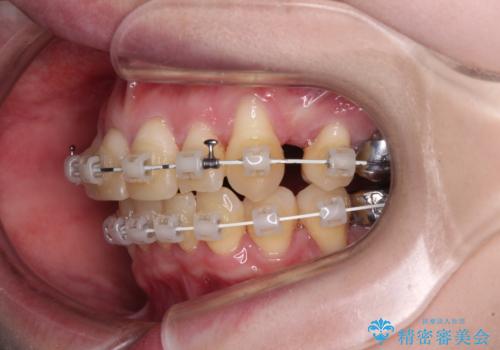

八重歯と先天欠損の歯列 ワイヤー矯正ですっきりと

- 矯正装置

- 審美装置

- 1年7ヶ月

- 八重歯と正中のズレを気にして来院された患者様です。

上顎左側が八重歯になっており、上顎正中が左側にずれていました。

上顎左側の第一小臼歯を抜歯し、補助装置を用いて正中位置を改善しながら八重歯を解消していくこととしました。

下顎前歯が1本欠損していたため、上下正中の位置が合わせるという目標はなく、鼻筋に上顎正中を合わせていくように移動を行いました。